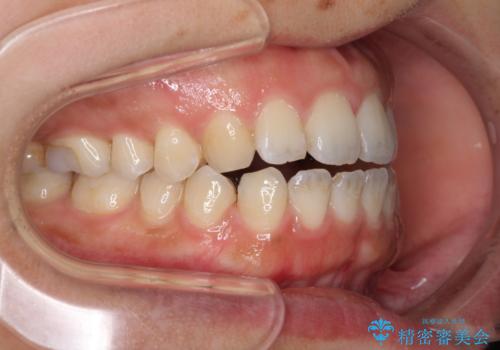

全く目立たないワイヤー矯正 上下リンガル矯正

- 上下の前歯のでこぼこを気にして来院された患者様です。

結婚式が近いこともあり、全く目立たない裏側矯正により口元を整えることとしました。

下顎が左側にずれているため、裏側矯正ということもあり咬み合わせを整えるのに時間がかかってしまいました。